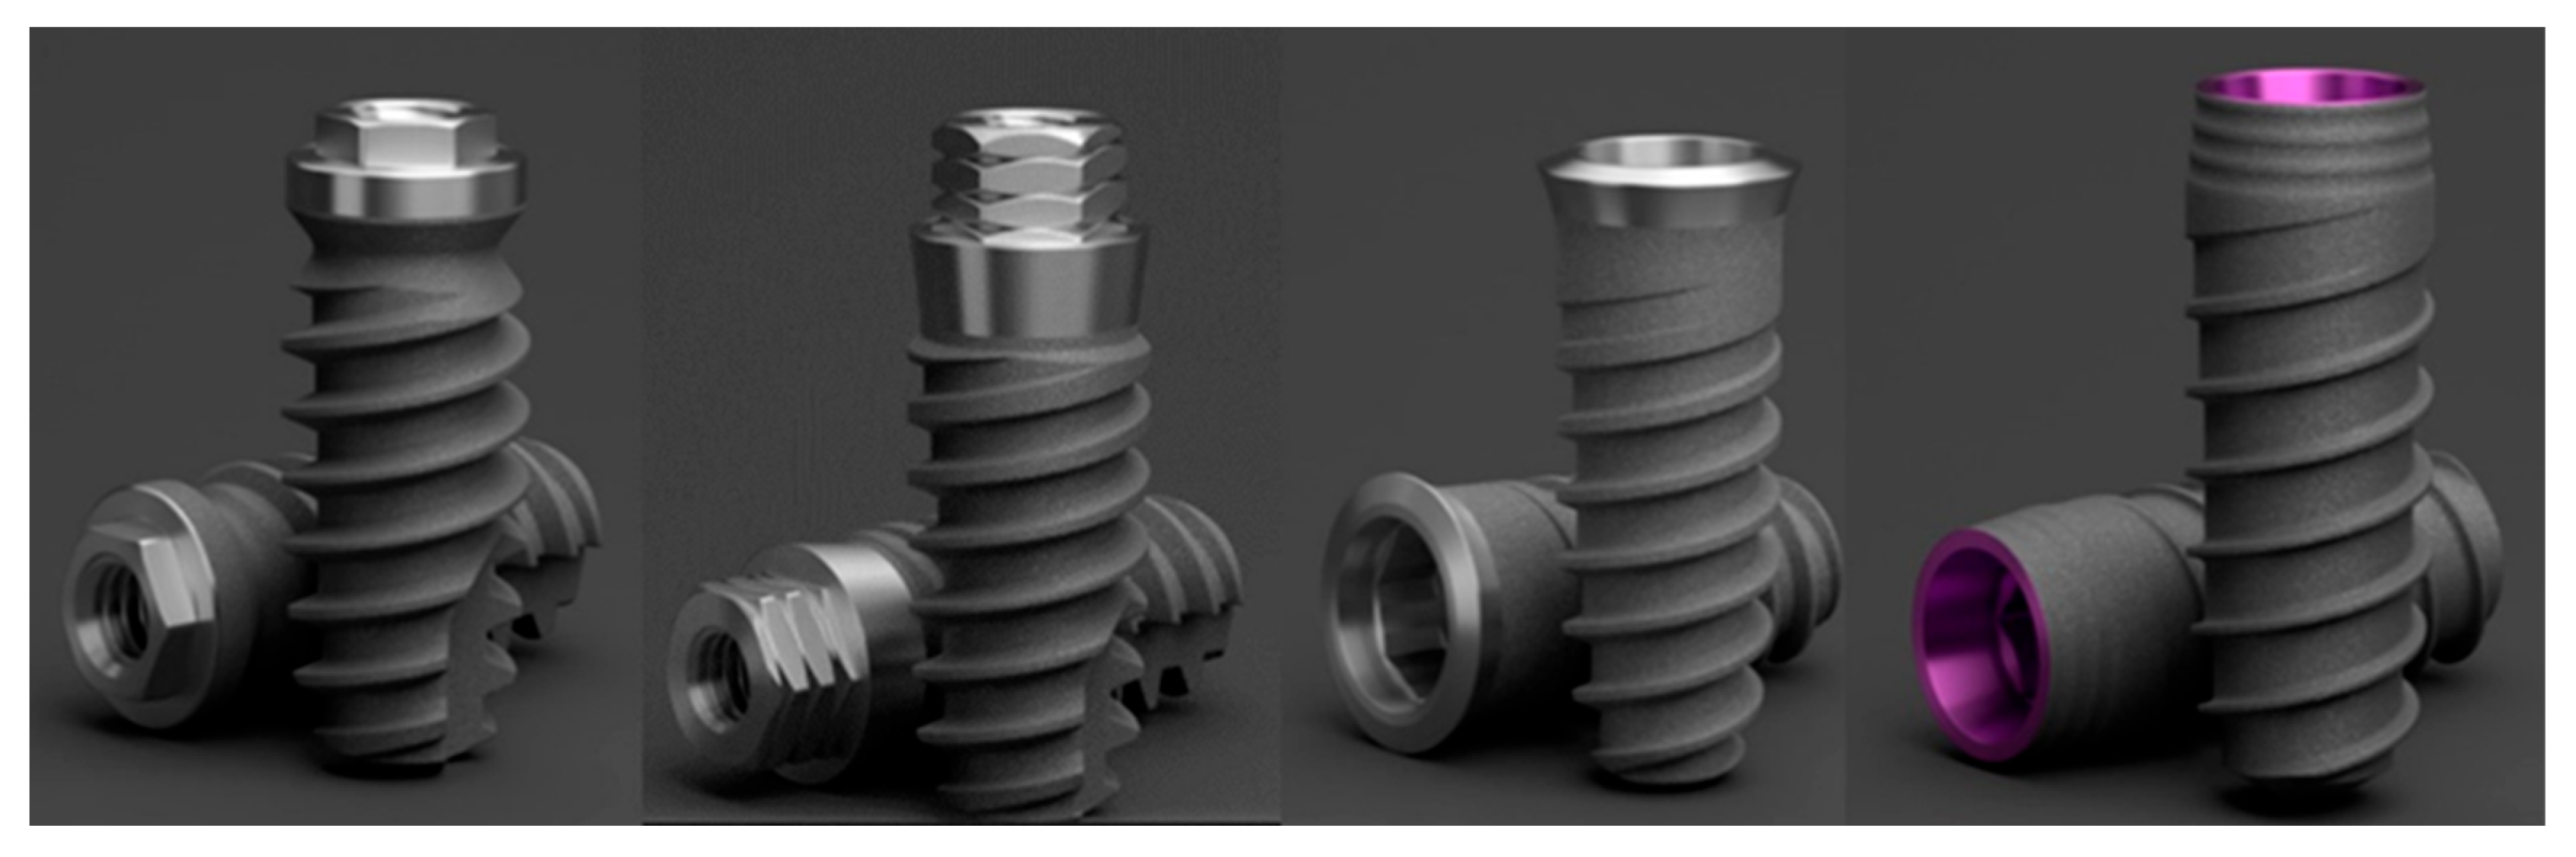

2.1. Description of Implants

3.1.1. KL Implants

3.1.2. Essential Implants

3.1.3. SK2 Implants

3.1.4. Vega Implants